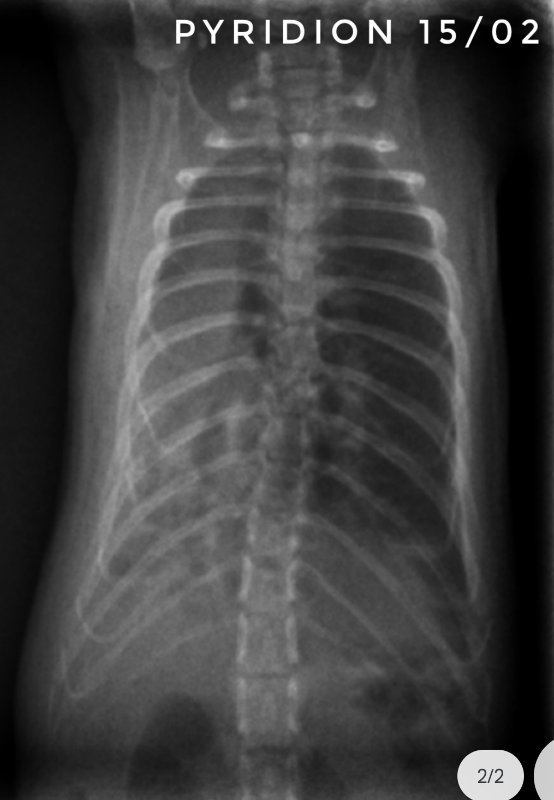

Toujours pour ceux que ça intéresse, les dernières  radios et le suivi du poids (Pyridion a commencé à perdre du poids le 04 mars, traitement changé le 08)

Pyridion a eu un vrai mieux la semaine dernière et grosse dégradation là. Les radios n'ont pas bougé depuis 3 semaines...

Bon, Drupe et Caryopse continue de prendre du poids régulièrement, mais Pyridion est en chute libre... Entre le 1er et le 4 mars, il a pris de 220 à 230g, on était super contents, puis il a perdu petit à petit, le 8 il n'était plus qu'à 215g, on a changé de traitement, il est aujourd'hui à 197g... Mardi et jeudi il avait repris un peu donc comme j'ai eu du mal à bien lui donner le marbofloxacine (seule la citation des molécules actives est autorisée) au début, je me suis dit que ça commençait à faire effet, mais en fait il continue à perdre... je contacte mon veto demain (la prochaine visite était prévue le 28...).